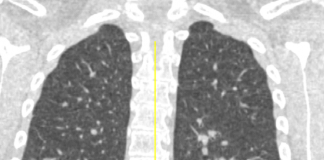

Paziente di sesso maschile, di 42 anni, senza comorbidità, da 5 giorni affetto da febbre, tosse ed iperpiressia...